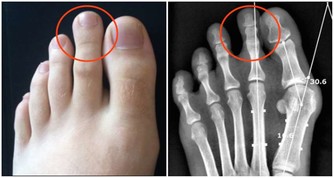

心臟大小合理

心臟的大小可以用心胸比率(心臟的橫徑與胸腔橫徑之比)來衡量。正常人心臟的比率為0.42~0.48,如果超過0.5即為不正常。此外,還可用一隻手攥拳,用另一隻手包住它,其大小就約等於你的心臟。成年人心的長徑約12~14公分,橫徑9~11公分,前後徑6~7公分。